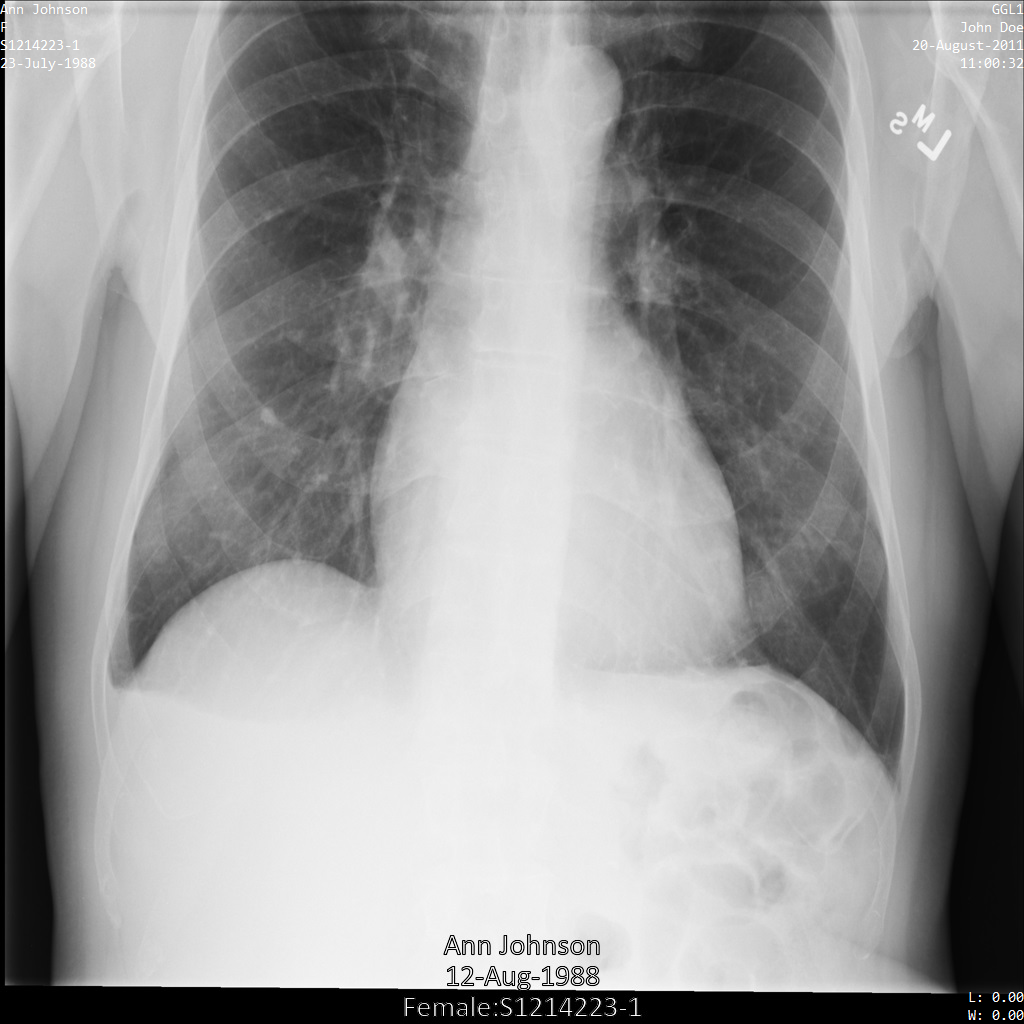

Contoh berikut menunjukkan cara melakukan de-identifikasi set data yang berisi penyimpanan DICOM dan data DICOM dengan menghapus semua tag dalam removelist. Tag yang tidak ada dalam removelist tidak berubah.

Setelah mengirimkan gambar ke Cloud Healthcare API, gambar akan muncul

seperti berikut. Dari tag yang diberikan dalam removelist, hanya PatientBirthDate

yang dihapus dalam gambar, karena hanya tag tersebut dari removelist yang

sesuai dengan metadata yang terlihat dalam gambar.

Meskipun PatientBirthDate di sudut atas gambar telah

disamarkan sesuai dengan konfigurasi dalam removelist, PHI

yang tercetak di bagian bawah gambar tetap ada. Untuk juga

menghapus teks sisipan, lihat Menyamarkan teks sisipan dari gambar.